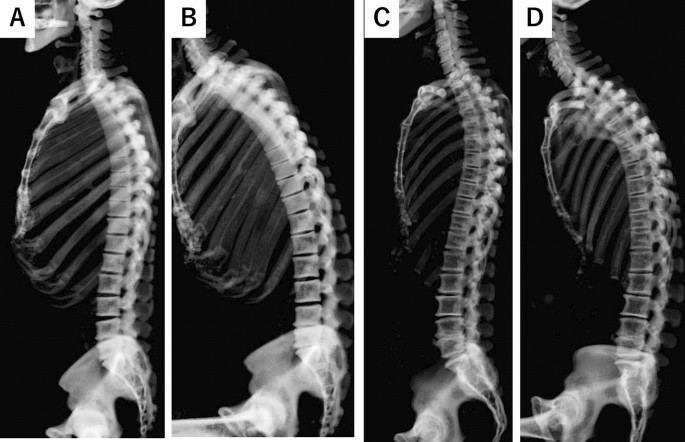

Comparisons of the change of regional lumbar spinal parameters by posture between male and female subjects

The representative CT images were shown in Figs. 2 and 3. Females had a significantly larger LL than males during standing (46.6° vs. 40.4°, p = 0.03, Table 2). However, when transitioning to sitting, females exhibited a larger reduction rate in LL compared to males, though not statistically significant (− 91.4% vs. − 80.2%, p = 0.052, Table 2). Additionally, while there was a significant decrease in the reduction rate for elderly males, elderly females retained a similar reduction rate in LL compared to young females (− 90.9% vs. − 53.0% for males and − 95.8% vs. − 84.0% for females, p = 0.01, 0.29). (Supplemental Table 2).

Representative cases of the change of spinal alignment by posture in the young subjects. (A) The standing whole spine CT of 32-year-old male. (B) The sitting whole spine CT of 32-year-old male. (C) The standing whole spine CT of 38-year-old female. (D) The sitting whole spine CT of 38-year-old female. A significant spinal alignment change was observed in a female patient when transitioning to a sitting position.

representative cases of the change of spinal alignment by posture in the elderly subjects. (A) The standing whole spine CT of 74-year-old male. (B) The sitting whole spine CT of 74-year-old male. (C) The standing whole spine CT of 72-year-old female. (D) The sitting whole spine CT of 72-year-old female. A significant spinal alignment change was observed in a female patient when transitioning to a sitting position.

For SS, the study found significantly larger delta values in females compared to males among both the overall participant group and the elderly subset. Specifically, the difference was − 23.9° in young males versus − 30.4° in females, and − 10.1° in elderly males versus − 24.8° in elderly females, and − 15.2° in males versus − 26.4° in females for the overall group, with P-values of 0.11, 0.04 and 0.04, respectively. Similarly, for PT, significantly larger delta values were observed in females compared to males in both the overall participant group and the elderly subset. The delta values were 24.4° in young males versus 33.0° in young females, and 12.7° in elderly males versus 25.7° in elderly females 16.2° in males versus 28.7° in females for the overall group, with P-values of 0.09, 0.04 and 0.04, respectively. Lastly, PI was significantly larger in females than in males, with values of 42.3° for males and 47.7° for females, and a P-value of 0.048 (Table 2). Overall, these findings suggest that females exhibited a larger lordosis to match their higher PI and retained this flexibility until their elderly years.